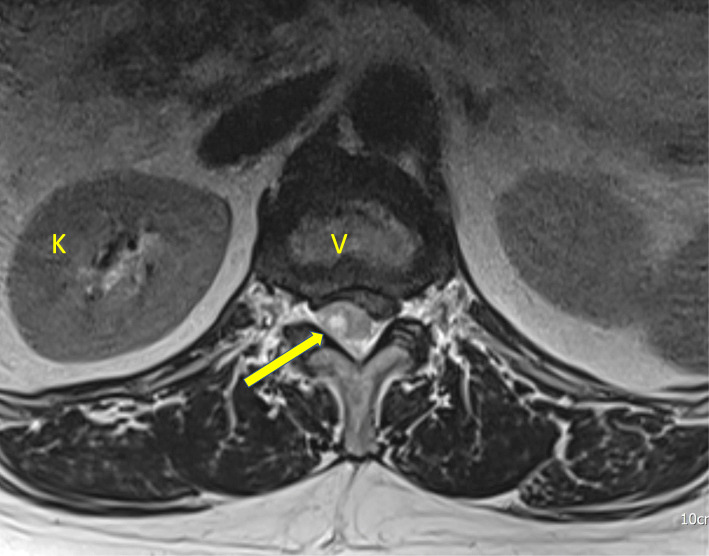

Fig. 1.

Lumbosacral magnetic resonance imaging without contrast, axial view. V: vertebrae, K: kidney, arrow: epidural hematoma occupies the spinal canal and compresses the spinal cord